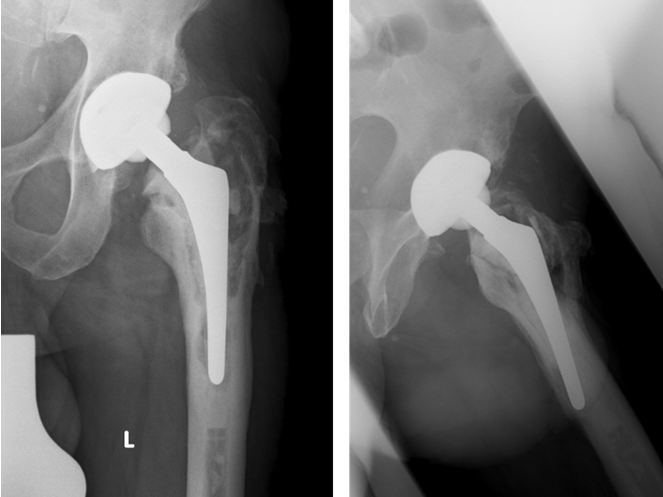

- 6/2010: Cementless revision THR (Acetabular component: Metallsockel 2000, Orthodynamics, Luebeck, Germany; Femoral component: Restoration Modular Stryker, Mahwah, NJ, USA). Microbiology: Five tissue samples and PCR/culture of the spacer sonication fluid without detection of microorganisms

- 7/2011: Clinical and radiological follow-up one year after reimplantation: no clinical or laboratory signs of a relapse of the periprosthetic infection. The X-rays (Figure 4 [Fig. 4]) show moderate ossifications of the soft tissue around the femoral diaphysis without clinical relevance. No signs of implant-loosening or migration.

Figure 4: Cementless total hip revision implant: radiological follow-up 1 year after implantation